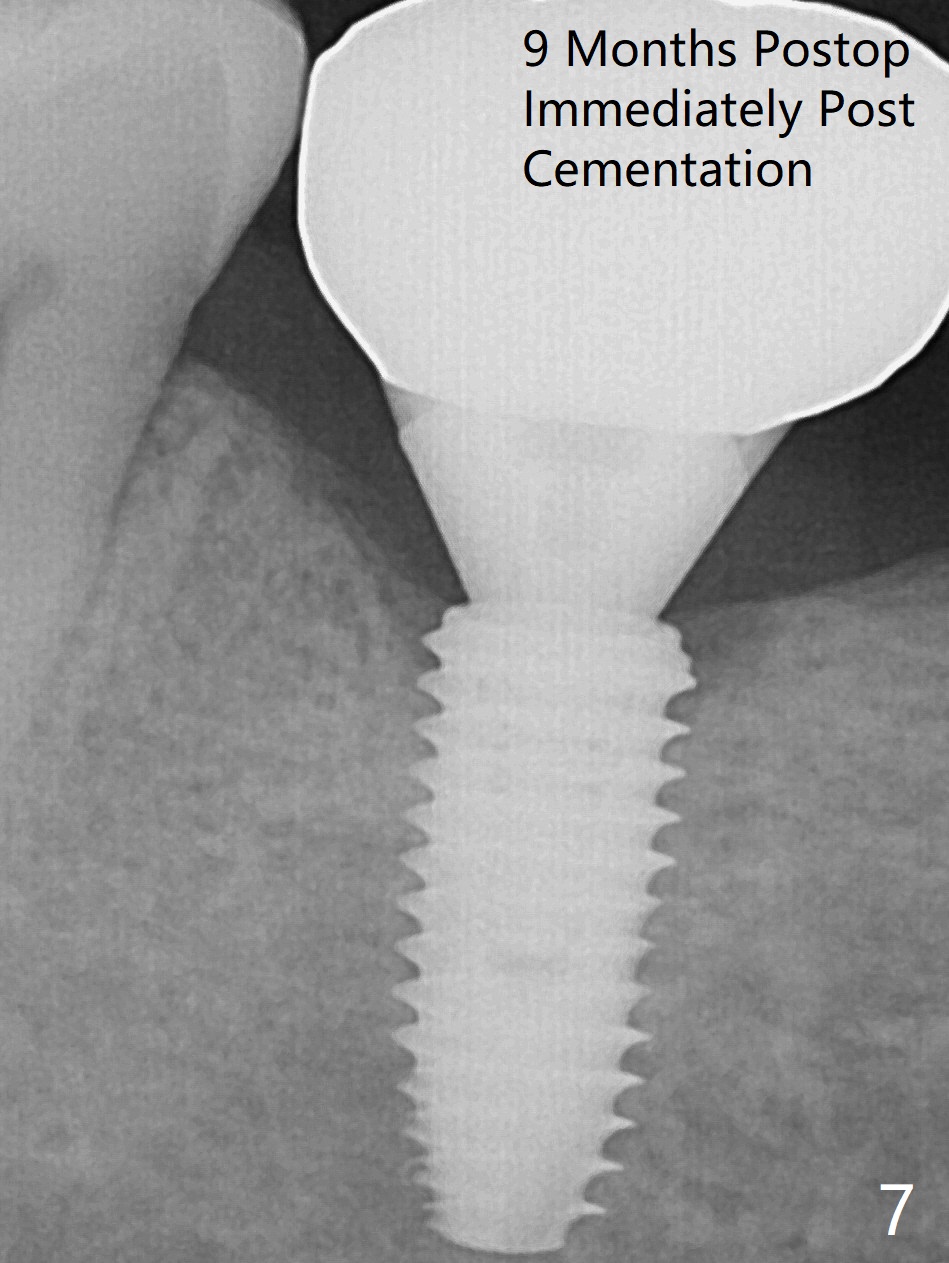

Because of severe pain, block anesthesia is administered prior to extraction. The mesial socket of the tooth #30 is deep with granulation tissue. A 4.5x10 mm dummy implant is placed with < 40 Ncm following sequential osteotomy until 4x13 mm over the septum (Fig.1 (low density)). After 4.5x13 mm drill, a 5x10 mm dummy implant is inserted with <40 Ncm (Fig.2). Since the Inferior Alveolar Canal is invisible (Fig.1,2 (pan should have been taken)), a 5x11.5 mm implant is placed with <20 Ncm. When a 6.5x5.5(3) mm abutment is placed, the underlying implant is turned (Fig.3). With collagen plug is placed in the distal socket and Vera graft around the implant, an immediate provisional is fabricated and relined. When it is seated, it has mobility. In fact the provisional should be locked into the edentulous area while it is malleable. To prevent low primary stability, osteotomy should be under prep, since the implant (red circle) contacts only two bony surfaces, i.e., the mesial (M) and distal (D) walls of the mesial socket (Fig.4 (occlusal view) black oval). There are gaps buccally (B) and lingually (L). In case of low stability, a healing screw or abutment should be placed; the remaining socket is closed with suture. The provisional is loose 19 days postop; it is removed by sectioning. A healing screw is placed. Twelve days later, the wound heals (Fig.5). The patient returns for uncover 8 months postop; although the implant has osteointegrated apparently, the crestal bone resorbs to the implant plateau level (Fig.6 arrow). It seems that the immediate implant should be routinely placed 2-3 mm deeper. The open margin is closed with composite when the abutment/crown is removed after cementation (Fig.7).